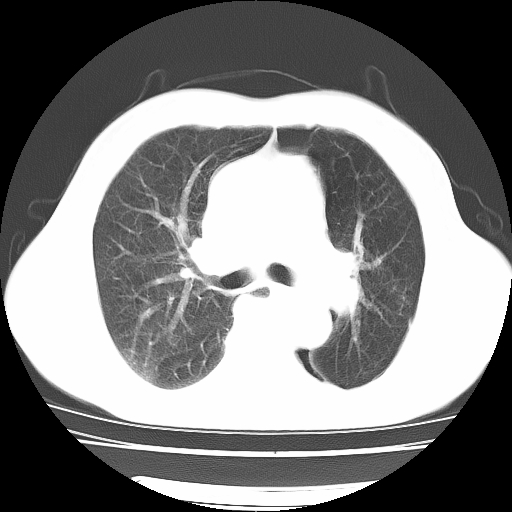

男,71岁,咳嗽,气喘10年,再发并咯血.胸片见气胸

考虑  左肺中心型肺癌伴阻塞性肺炎,肺不张,纵膈淋巴结肿大。慢支炎,肺气肿,左侧气胸肺压缩5%

左侧中央型肺癌伴纵膈淋巴结转移。

左肺中心型肺癌伴阻塞性肺炎,肺不张,纵膈淋巴结肿大

1)考虑左肺中心型肺癌伴阻塞性肺炎、左肺下叶肺不张、左侧肺气肿,纵膈淋巴结转移。2)左侧气胸(肺组织压缩约5%)。

左肺中心型肺癌伴阻塞性肺不张、肺气肿 。

1)考虑左肺中心型肺癌伴阻塞性肺炎、左肺下叶肺不张、左侧肺气肿,纵膈淋巴结转移。2)左侧气胸。